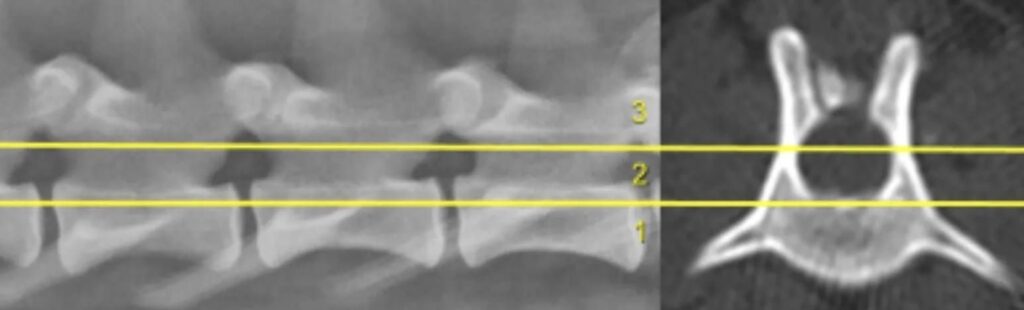

Το «μοντέλο των τριών διαμερισμάτων» χρησιμοποιείται για την αξιολόγηση της αστάθειας:

- Κοιλιακό διαμέρισμα: κοιλιακό τμήμα του σώματος του σπόνδυλου, δίσκος, κοιλιακός επιμήκης σύνδεσμος

- Μέσο διαμέρισμα: Ραχιαίο τμήμα του σώματος του σπονδύλου και του δίσκου, ραχιαίος επιμήκης σύνδεσμος

- Ραχιαίο διαμέρισμα: αυχένες των σπονδύλων, αρθρικές αποφύσεις, πέταλα σπονδυλικού τόξου, ακανθώδεις αποφύσεις, μεσοτόξιοι ή ωχροί σύνδεσμοι (interarcuate ligaments)

Η προσβολή δύο ή περισσοτέρων διαμερισμάτων υποδηλώνει αστάθεια.

Στην πλάγια ακτινογραφία της σπονδυλικής στήλης απεικονίζονται τα 3 διαμερίσματα της σπονδυλικής στήλης για την εκτίμηση της σταθερότητας. Η προσβολή δύο ή περισσοτέρων διαμερισμάτων υποδηλώνει αστάθεια

Το «σύστημα των τριών στηλών του σπονδυλικού σωλήνα». Η ραχιαία στήλη περιλαμβάνει τα πέταλα του σπονδυλικού τόξου (laminae), τους αυχένες (pedicles) (παριστούν το τμήμα του πετάλου που γίνεται στενότερο και προσφύεται στο σπονδυλικό σώμα), τις αρθρικές αποφύσεις, τους μεσοτόξιους ή ωχρούς συνδέσμους (interarcuate ligaments) (παρεμβάλλονται μεταξύ των πετάλων των σπονδύλων καλύπτοντας τα μεταξύ τους μεσοτόξια διαστήματα) και τις ακανθώδεις αποφύσεις.Η μέση στήλη περιλαμβάνει τη ραχιαία επιφάνεια του σπονδυλικού σώματος, το ραχιαίο τμήμα του μεσοσπονδυλίου δίσκου και το ραχιαίο επιμήκη σύνδεσμο. Η κοιλιακή στήλη περιλαμβάνει το κατώτερο τμήμα του σπονδυλικού σώματος και του μεσοσπονδυλίου δίσκου και τον κοιλιακό επιμήκη σύνδεσμο.